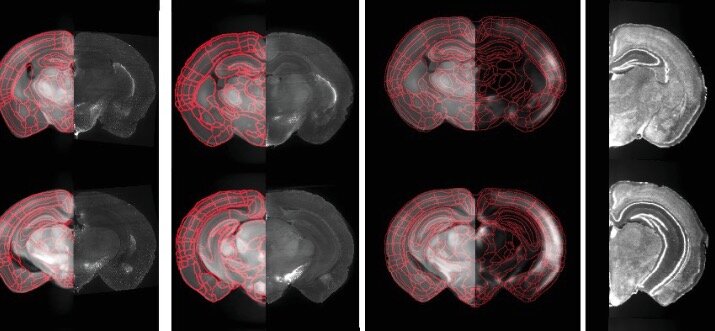

Группа исследователей, в том числе Стивен Фелпс (Steven Phelps) из Техасского университета (University of Texas) в Остине, создала первую карту областей головного мозга, которые активны у степных полевок во время спаривания и образования пар.

Исследователи обнаружили, что связывающиеся полевки испытывают бурную мозговую активность, распределенную по 68 различным областям мозга, которые составляют семь мозговых цепей. Активность мозга коррелирует с тремя стадиями поведения: спариванием, установлением связи и возникновением стабильной, прочной связи.

Большинство из этих областей мозга, которые выявили исследователи, ранее не были связаны, поэтому карта показывает новые места в человеческом мозге, на которые стоит обратить внимание, чтобы понять, как мы формируем и поддерживаем близкие отношения.

Исследователи смогли с высоким разрешением определить, какие клетки головного мозга были активны в мозге полевок на различных этапах процесса, который приводит к образованию связей и включает их.

Подобный метод применен к степным полевкам впервые. Изучив более 200 степных полевок несколько раз во время спаривания и сближения, исследователи получили беспрецедентный и фундаментальный набор данных.